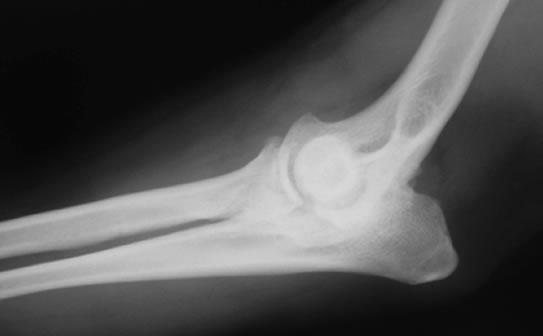

肘関節形成不全症 / FCP(内側鈎状突起分離症)

症状:5〜11ヶ月齢での前肢をかばう歩行、運動後や休息後に前肢をかばう、歩行時に頭を上下させるといった症状がみられます。診断がつかず関節炎が進行した中年以降に再び跛行することが多いです。

肘関節形成不全症とは

肘関節形成不全とはFCP(内側鈎状突起分離症)、UAP(肘突起分離症)、OCD(上腕骨内顆の離断性骨軟骨症)、肘関節不一致の4つの疾患が複合した肘関節疾患です。単独でみられる場合もあれば、併発して見られる場合もあります。

FCP(内側鈎状突起分離症)とは

肘関節形成不全症のうちFCPは、尺骨の内側鈎状突起の癒合障害により、尺骨から浮き上がった骨片によって関節軟骨の損傷が起こり、痛みが生じる病気です。

診断

レントゲン検査、関節鏡検査

治療

関節鏡視下で尺骨から浮き上がった骨片を切除する等の治療をおこないます。大型犬の成長期の跛行は消炎鎮痛剤等による対症療法ですませず、跛行原因の早期診断、早期治療が重要です。